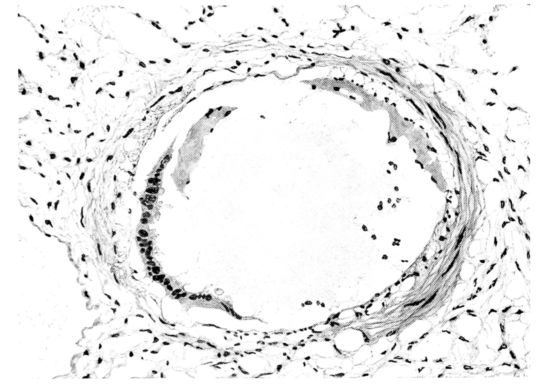

FIG. I. AUTOPSY NO. 99. ACUTE HEMORRHAGIC AND ULCERATIVE LARYNGOTRACHEITIS.

FIG. I. AUTOPSY NO. 99. ACUTE HEMORRHAGIC AND ULCERATIVE LARYNGOTRACHEITIS.

Early in the disease the congestion and the hemorrhages that have been described in the mucous membrane of the nasopharynx (14 and 94) are also conspicuous features in the lining of the trachea and bronchi (Fig. I). This membrane is swollen, turgid, red, and covered by a copious, mucous exudate which may be clear, but much more frequently is blood-stained or opaque and yellowish in color. The blood, variable in amount, may be fresh and red; and after the mucous exudate on the surface is removed, more intense red foci stand out on the congested base (47, 90, 157). Frequently, as the bronchi are approached, the red color of the mucosa becomes more intense and may have a garnet tinge. Membranes such as are encountered in the more usual necrotizing inflammatory processes, like diphtheria, have not occurred in the trachea and larger bronchi in this series (108, 128, 157).[3] The exudate peels off readily, and as indicated above, leaves a velvety red surface, 14dotted here and there with darker or more intensely red foci. Small ulcerations of the mucosa occur, but are inconspicuous (82, 156). As the finer ramifications of the bronchi are approached, the accumulation of the exudate in their lumina becomes more and more marked, and on cross section of the lung, they often stand out conspicuously on account of their increased size and projecting, seromucous, blood-stained content (101, 149, 162).